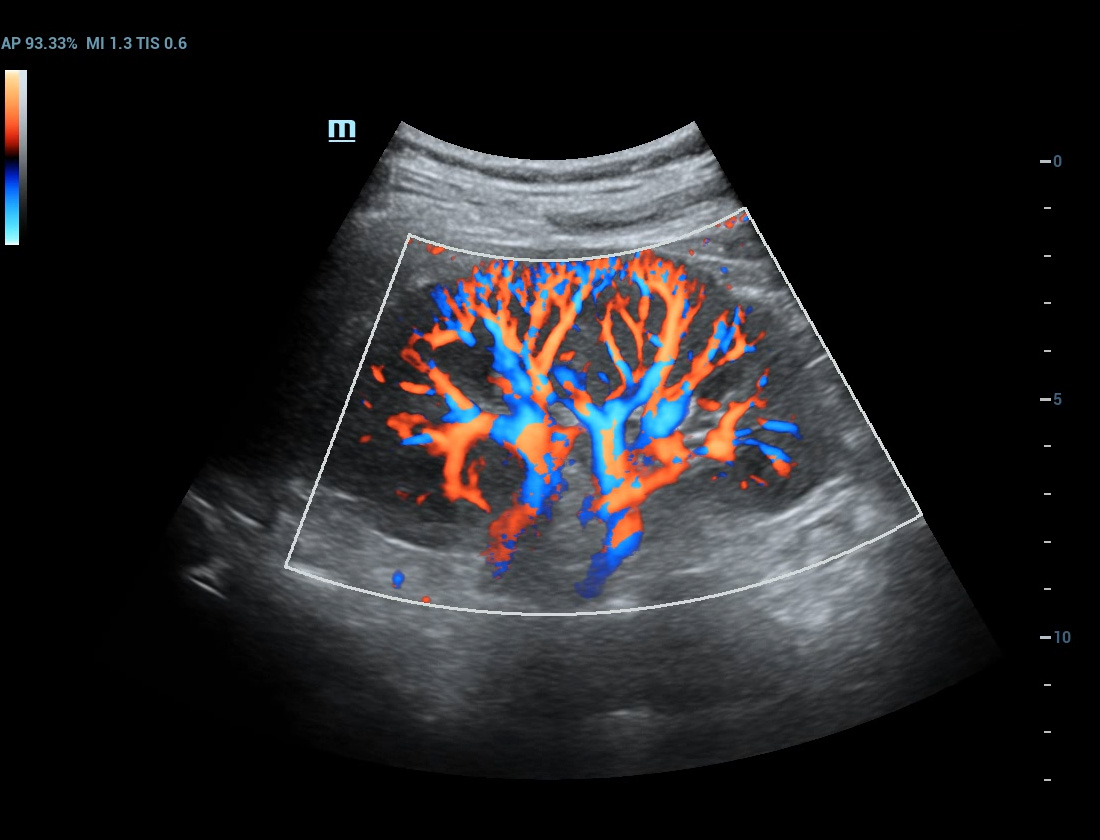

Ultra Micro Angiography (UMA)

UMA migliora la sicurezza diagnostica ampliando la visibilitĂ dei flussi sanguigni fino al livello dei vasi piĂč piccoli, con una sensibilitĂ e una risoluzione superiori.

Rene sUMA

Massa mammaria pUMA

Tumore alla tiroide sUMA